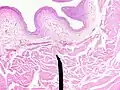

When viewed under a microscope, the bladder can be seen to have an inner lining (called epithelium), three layers of muscle fibres, and an outer adventitia.[8]

The inner wall of the bladder is called urothelium, a type of transitional epithelium formed by three to six layers of cells; the cells may become more cuboidal or flatter depending on whether the bladder is empty or full.[8] Additionally, these are lined with a mucous membrane consisting of a surface glycocalyx that protects the cells beneath it from urine.[14] The epithelium lies on a thin basement membrane, and a lamina propria.[8] The mucosal lining also offers a urothelial barrier against the passing of infections.[15]

These layers are surrounded by three layers of muscle fibres arranged as an inner layer of fibres orientated longitudinally, a middle layer of circular fibres, and an outermost layer of longitudinal fibres; these form the detrusor muscle, which can be seen with the naked eye.[8]

The outside of the bladder is protected by a serous membrane called adventitia.[8][16]

- Vertical section of bladder wall

- Layers of the bladder wall and cross-section of the detrusor muscle

- Anatomy of the male bladder, showing transitional epithelium and part of the wall in a histological cut-out